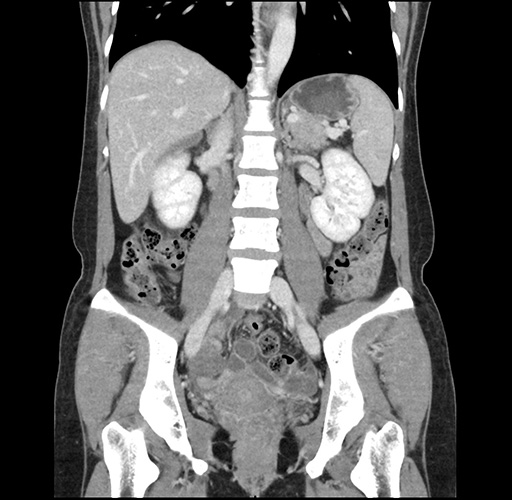

Imaging Analysis

Look through the patient's CT scan to identify any areas of concern for the necessary procedure.

Based on your CT findings, which issue(s) would give reason for "planned slowing down moment(s)" in this case?